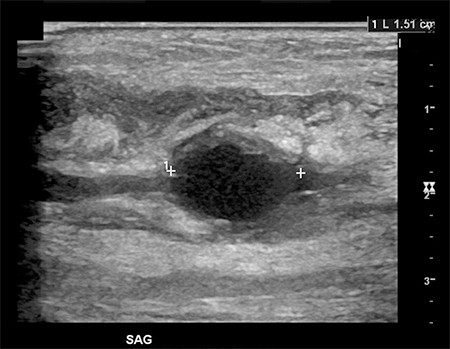

The patient was treated for sterile inflammation with ice and nonsteroidal anti-inflammatory analgesia. Two days later, his pain worsened and he presented to his primary care doctor. He was admitted to an outlying hospital where blood cultures revealed Staphylococcus aureus bacteremia. An arterial duplex showed a fusiform true aneurysm of the radial artery measuring a maximal diameter of 1.4 cm and a length of 1.5 cm (Figure 2 and 3). There was thickening of the aneurysm wall with no evidence of pseudoaneurysm or soft tissue abscess.

Figure 2. Sagittal plane ultrasound depicting radial artery fusiform aneurysm.